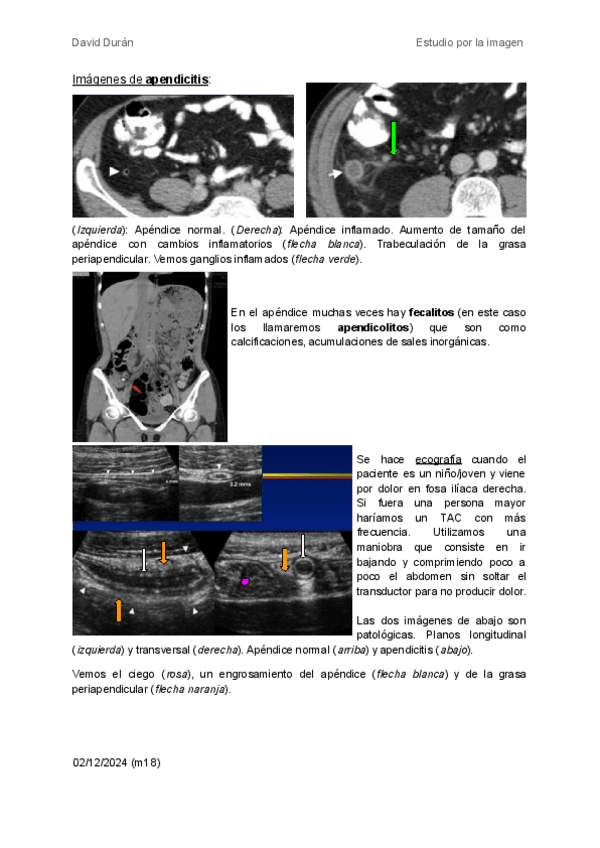

12 páginas

tubo-digestivo.pdf